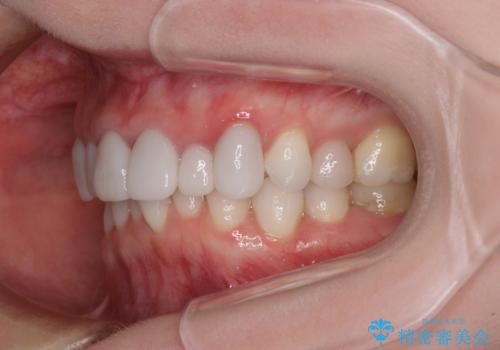

前歯のデコボコと奥歯の咬み合わせをインビザラインで改善

- 上下前歯のデコボコと奥歯の欠損を気にして来院された患者様です。

右下の欠損分は奥歯が倒れ込んでスペースがなくなっていたため、矯正治療により本来の位置に歯を移動させ、オールセラミックブリッジによる欠損補綴治療を行うこととしました。

全顎的にセラミッククラウンが多く装着されているため、インビザラインによる矯正治療を行うこととしました。

右下は移動量が多いため、十分な移動が達成されない場合はワイヤー装置を使用する予定としておりましたが、しっかりとマウスピースを装着してくださったため、前歯とともに十分に歯を動かすことができました。